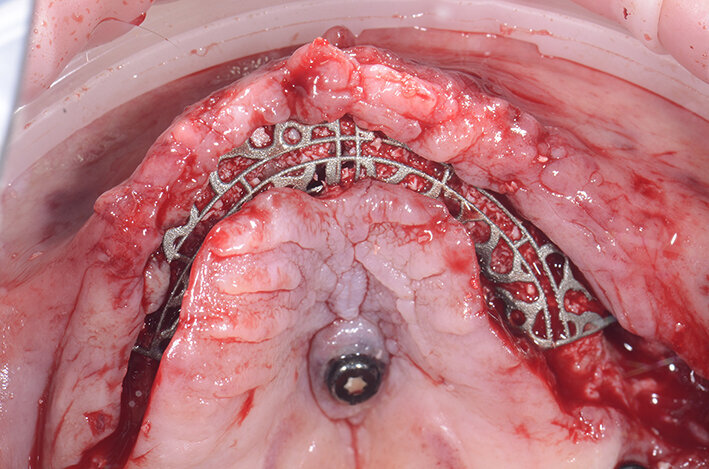

Una volta ottenute tutte le informazioni necessarie dei dati ossei (Cone Beam), della pianificazione protesica (STL della ceratura, dei tessuti e della situazione iniziale) l’azienda (ReOss, Filderstadt, Germany) invia il progetto della griglia Yxoss CBR che può essere visualizzato in maniera tridimensionale ed eventualmente modificato a discrezione del professionista. Suggerite le eventuali modifiche si esegue la validazione finale del progetto per la realizzazione della griglia (Fig. 8).Con la Customized Bone Regeneration (CBR) l’obiettivo della Rigenerazione Protesicamente Guidata in senso digitale viene così raggiunto. Le griglie sono prodotte attraverso una stampa tridimensionale e il loro fit al difetto è sempre accuratissimo consentendo di concentrare l’attenzione alle altre fasi dell’intervento.

Quello che troviamo è un’atrofia marcata in senso orizzontale nella zona della pre-maxilla che si estende anche nei settori latero-posteriori. Terminata la parte più importante dell’intervento ci dedichiamo a verificare il fit della griglia customizzata. È sorprendente ogni volta constatare l’alta affidabilità del posizionamento tridimensionale (Fig. 10). Il riempimento della griglia viene effettuato con osso autologo raccolto con Safe Scraper e con pinze ossivore che ci consentono anche di regolarizzare la cresta nella zona di intervento, miscelato al 50% con osso Bovino Deproteinizzato (Geistlich Bio-Oss, Geistlich Pharma).

In casi come questo, consiglio di non riempire completamente la griglia con l’innesto per evitare difficoltà nel posizionamento; prima di posizionare la griglia si colmano eventuali lacune nel riempimento con biomateriale (Geistlich Bio-Oss, Geistlich Pharma AG, Wolhusen, Switzerland). Dopo aver posizionato la griglia si utilizzano quattro viti, due vestibolari e due palatali, per renderla totalmente stabile (Figg. 11, 12). La griglia viene quindi ricoperta con una membrana in collagene riassorbibile Geistlich Bio-Gide (Geistlich Pharma AG) per migliorare la guarigione dei tessuti e per prevenire la migrazione del tessuto molle all’interno dell’innesto (Fig. 13).